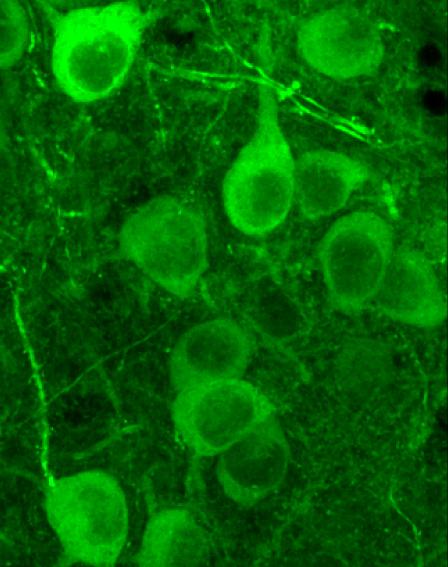

Using a miniaturized microscope imaging technique, Gründemann and Bitterman tracked neuronal activity in the amygdala of mice across different environments that prompted various internal states and behaviors. The results were rather unexpected: The researchers identified two large antagonistic sets of neurons - called ensembles - that were active in opposite behavioral states: When the mice were exploring their environment, neuronal ensemble 1 was active; when they were not exploring (meaning that they were in non-exploratory defensive states), neuronal ensemble 2 was active.